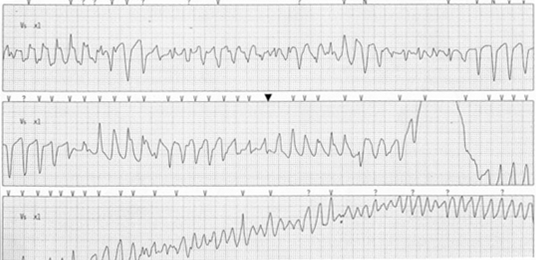

在到达ED的数小时内,患者经历了严重的心律失常(如下图所示)、心跳骤停,在200J直流电(DC)除颤后心律转复。

心电图显示的是什么节律?

答案:D. 尖端扭转型室性心动过速(TdP)演变为VF

患者的初始心电图(图1)可见窦性心律和原先存在的左束支传导阻滞(LBBB)。图2显示,尖端扭转型室性心动过速(TdP),也被称为多形性室性心动过速(VT),演变为VF,需要除颤治疗。

TdP的机制尚未被完全阐明;然而,先天性QT间期延长与主要影响钾、钠和钙通道的基因有关,使患者诱发TdP。随着QT间期延长,钙通道被认为开放时间更长,在交感神经张力增加时容易再激活。早期后除极(EAD)作为结果可以触发TdP,然后可变为VF(如图2),并导致猝死。